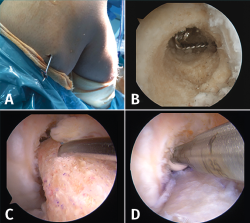

La cirugía de recambio de la plastia en un tiempo se inicia habitualmente con una revisión artroscópica convencional a través de los portales anteromedial y anterolateral. Después de la revisión artroscópica, se realiza la limpieza de los restos de la plastia previa, se retira el material de fijación y, posteriormente, se reconstruye el LCA con la nueva plastia (Figura 6).

Figura 6. Cirugía de revisión del ligamento cruzado anterior (LCA) en un tiempo. A: retirada del material de fijación previo. Casualmente, al utilizar el mismo túnel femoral la aguja guía permitió localizar y extraer el implante de fijación extracortical; B: restos de material en el túnel femoral que deben retirarse previamente a la introducción de la nueva plastia; C-D: el sobredimensionamiento del túnel femoral previo puede compensarse con un taco óseo de mayor diámetro asociado a un tornillo interferencial.

En cuanto al túnel óseo femoral, cuando está localizado en la posición correcta, se suele realizar el nuevo túnel óseo con un diámetro mínimamente superior al previo con el objetivo de retirar los restos de la plastia. La longitud del nuevo túnel dependerá de la plastia que el cirujano haya escogido para la cirugía. En el caso de un injerto con taco óseo, este se ajustará al diámetro del túnel realizado y, posteriormente, se fijará con un tornillo interferencial o bien un sistema de fijación cortical externa en el fémur. Cuando el túnel femoral se encuentre lejos de la localización del nuevo túnel, se puede rellenar el túnel previo con injerto óseo o un tornillo interferencial, con el fin de evitar la fractura de la pared del nuevo túnel. Esto puede suceder cuando se realiza una revisión sobre una técnica de reconstrucción transtibial previa (Figura 7).

Figura 8. Cirugía de revisión del ligamento cruzado anterior (LCA) en dos tiempos. A-B: aloinjerto preparado y rellenando el túnel femoral; C-D: relleno del túnel tibial con aloinjerto.